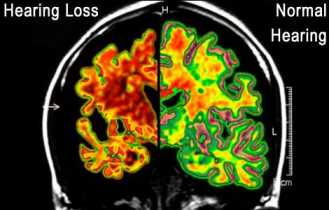

But it may increase your risk of developing dementia.

Image Source: Audiology and Hearing Aid Centre